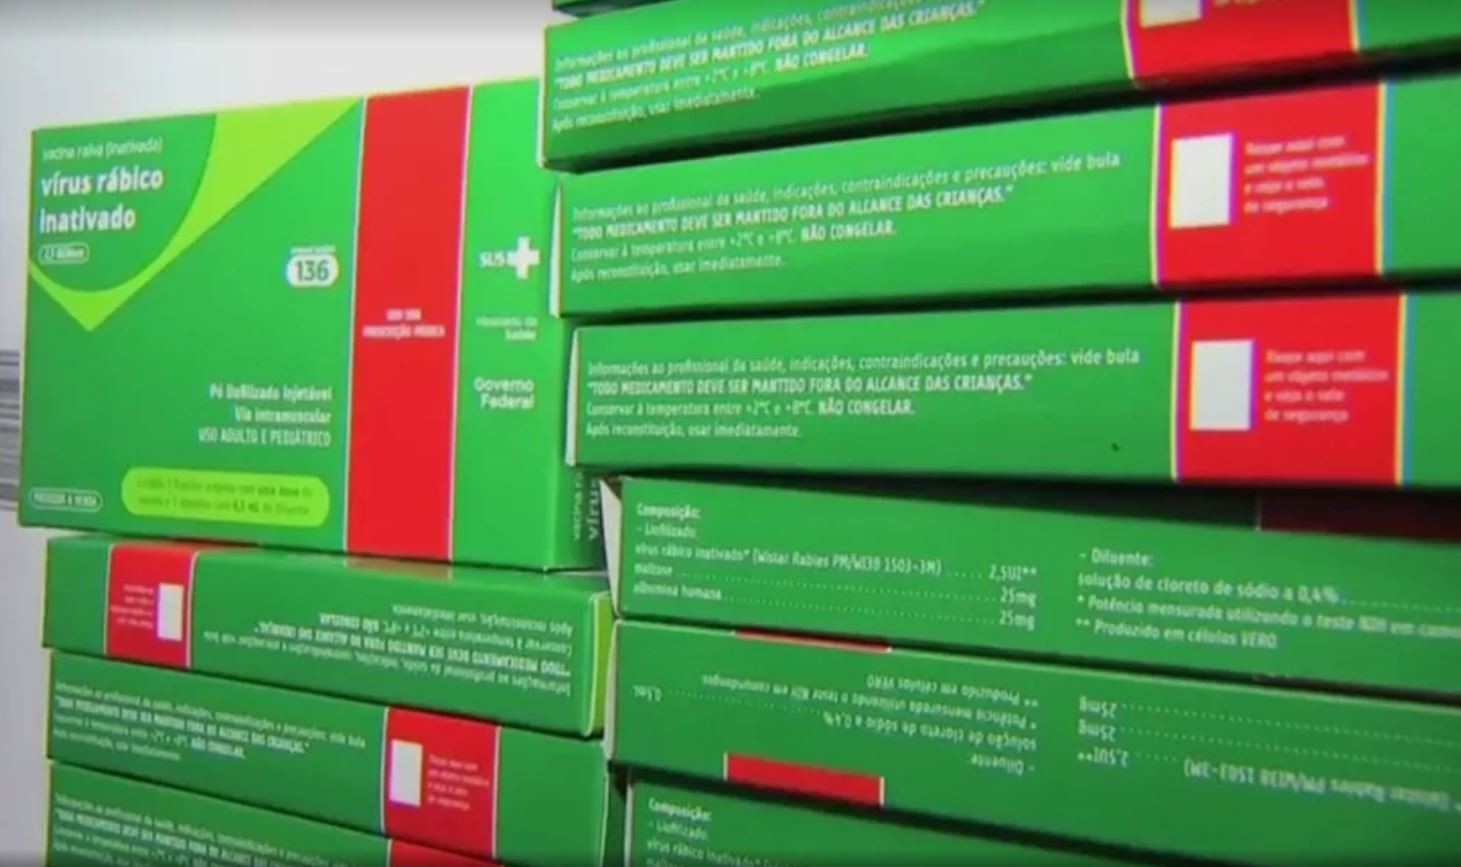

Natal passa a aplicar vacina antirrábica em profissionais que trabalham com banho e tosa de cães e gatos

Natal passa a aplicar vacina antirrábica em profissionais que trabalham com banho e tosa de cães e gatosAuxiliares veterinários também foram incluídos no grupo que vai receber vacina. Antes, apenas veterinários, biólogos e profissionais de laborató...